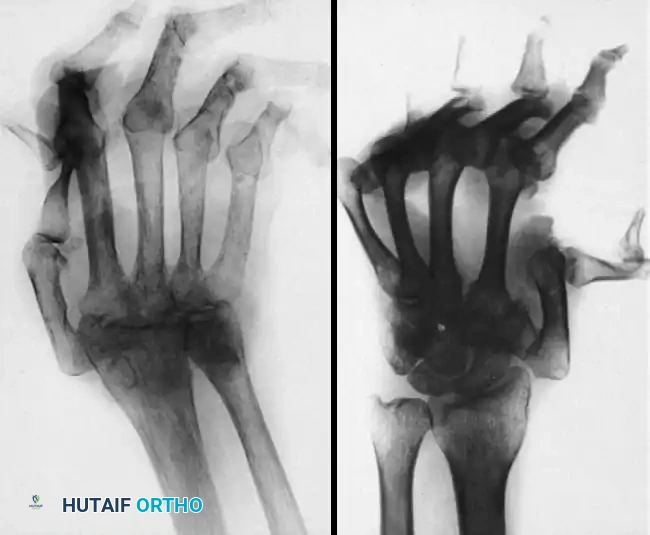

FIGURE 3: Typical radiographs of the hand and wrist in patients with systemic lupus erythematosus (SLE). Note the severe joint dislocations and ulnar drift without the erosive changes or joint space narrowing characteristic of psoriatic or rheumatoid arthritis.

In advanced psoriatic arthritis, profound joint destruction leads to subluxation and dislocation, particularly at the metacarpophalangeal (MCP) and interphalangeal (IP) joints.

FIGURE 4: Severe metacarpophalangeal joint dislocations and thumb interphalangeal joint destruction in advanced psoriatic arthritis.

Clinical Pearl: When evaluating a patient with severe hand deformities, the presence of joint subluxation without significant erosions should immediately raise the suspicion of SLE (Jaccoud's arthropathy), whereas profound osteolysis with periosteal reaction points toward psoriatic arthritis.